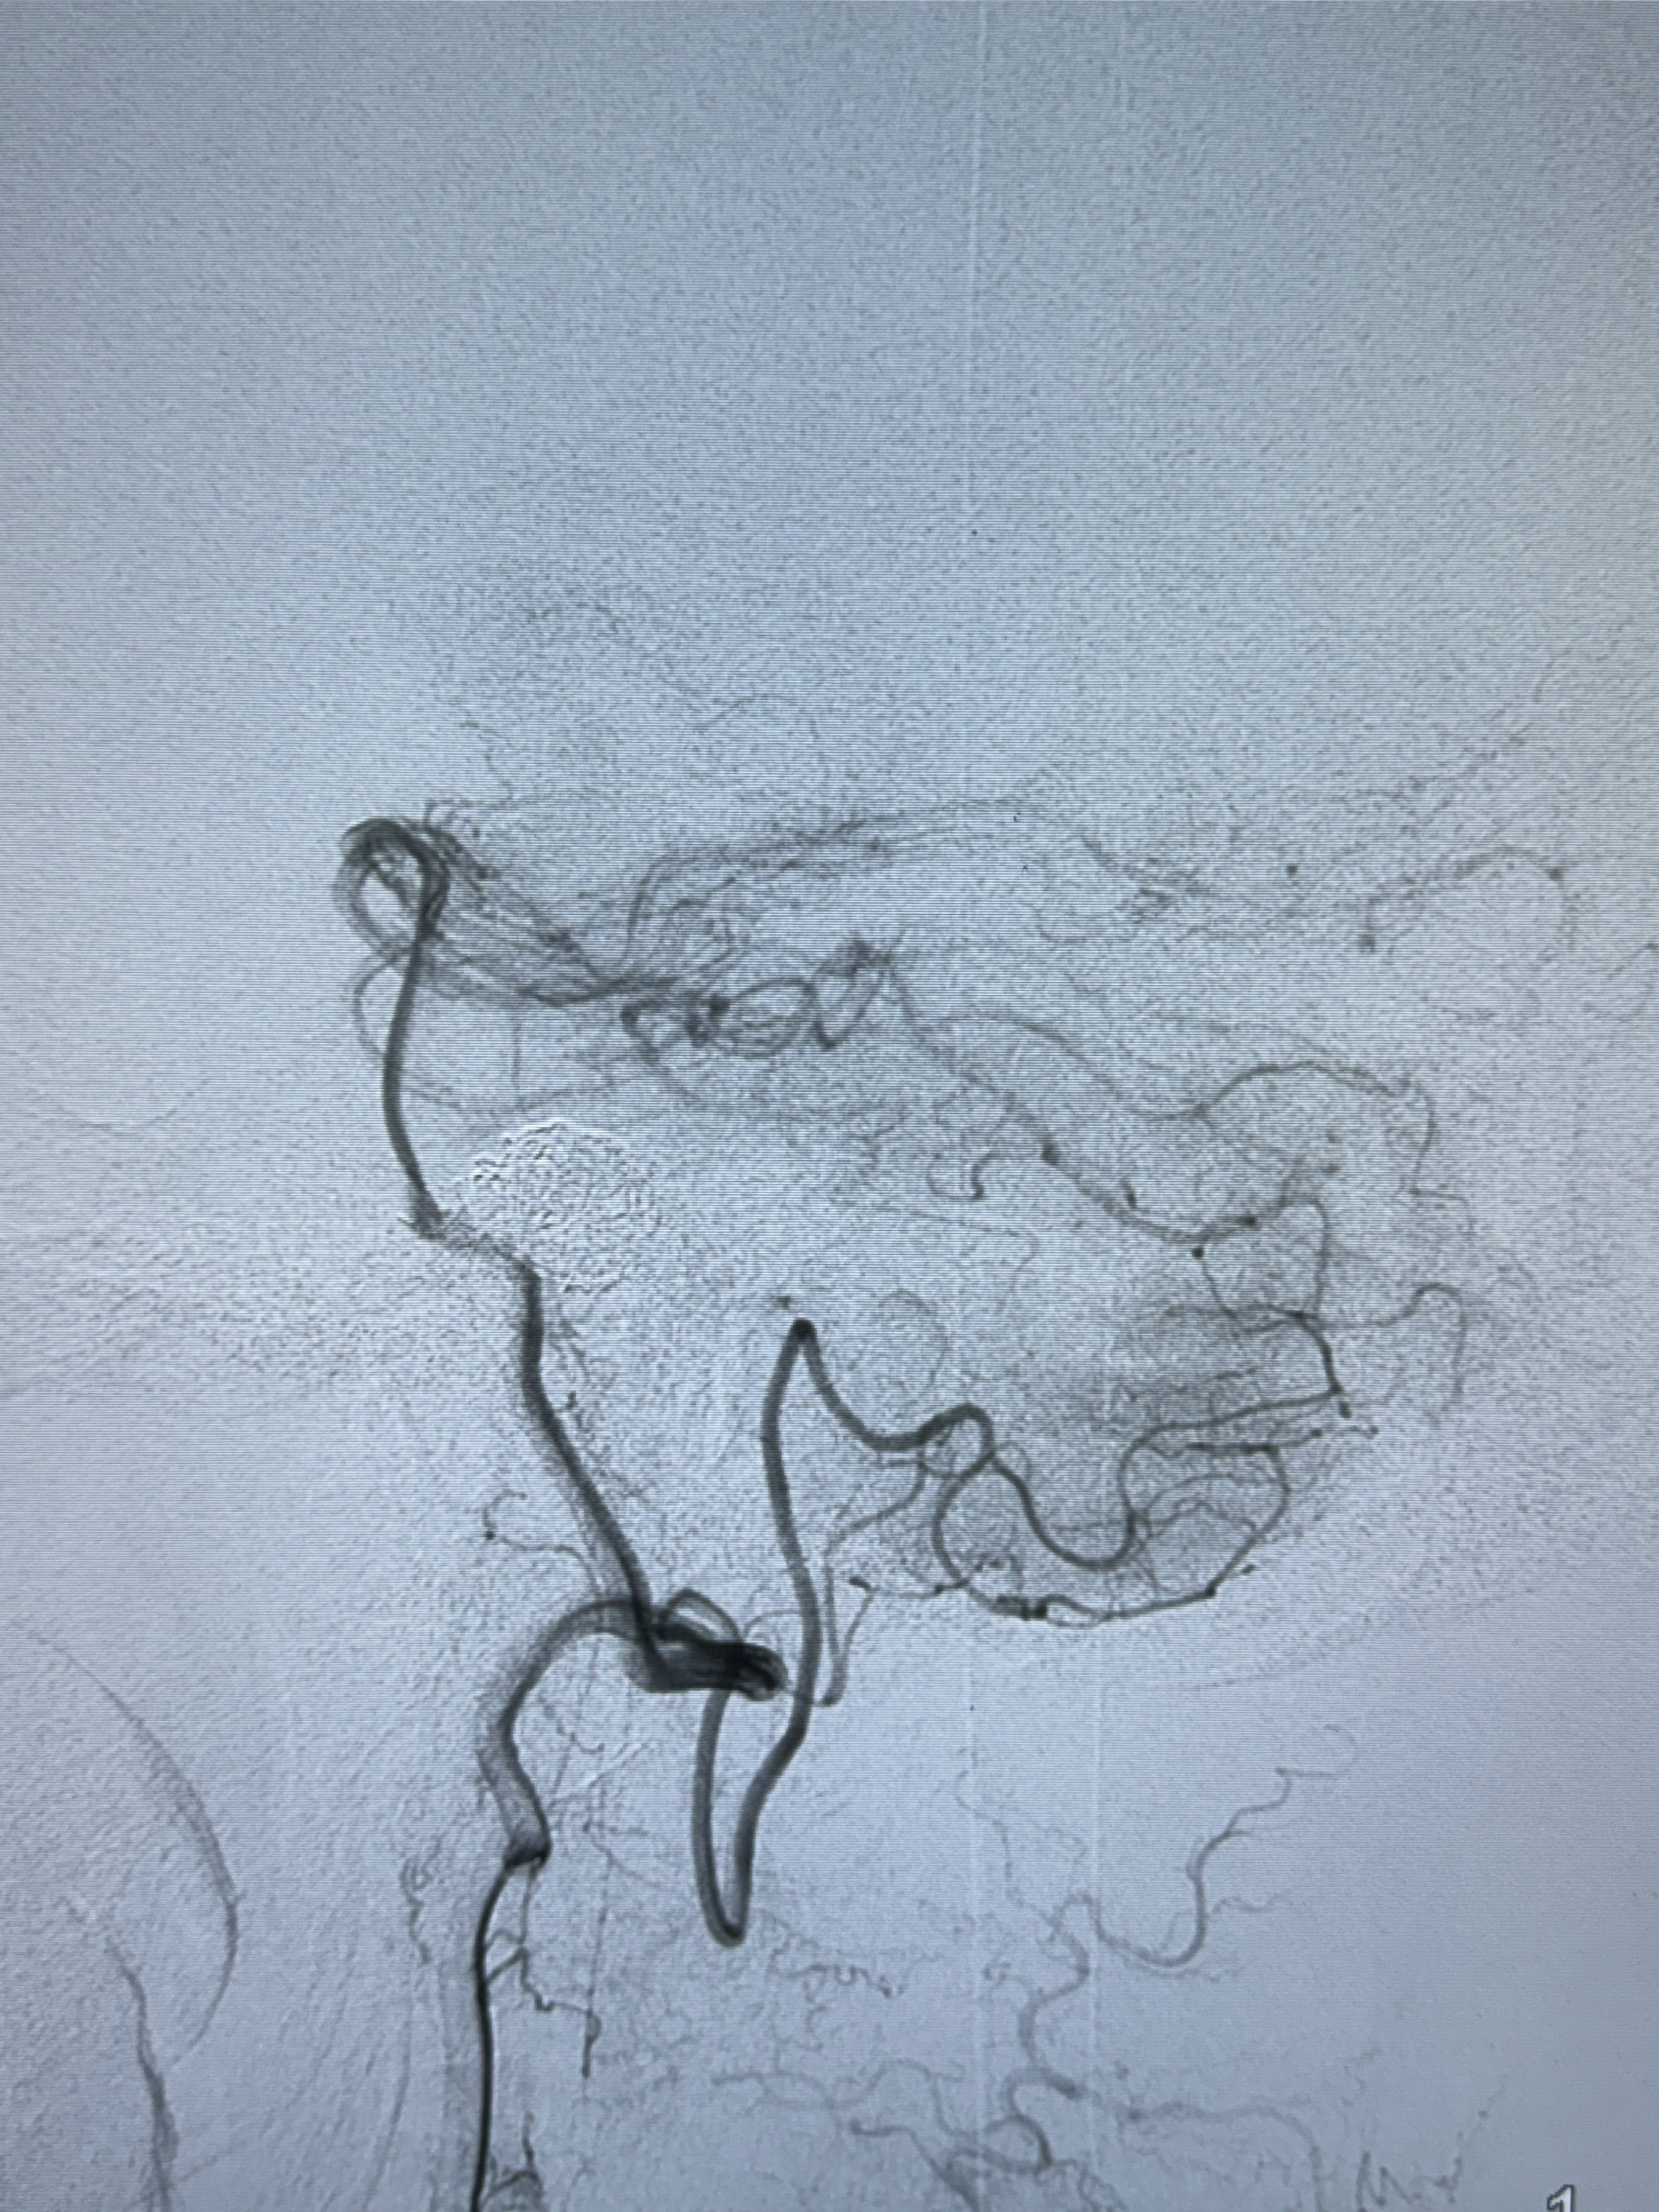

2024-01-08DSA:右侧椎动脉V4段夹层动脉瘤双支架辅助弹簧圈栓塞术后

患者支架辅助治疗后18个月,动脉瘤痊愈